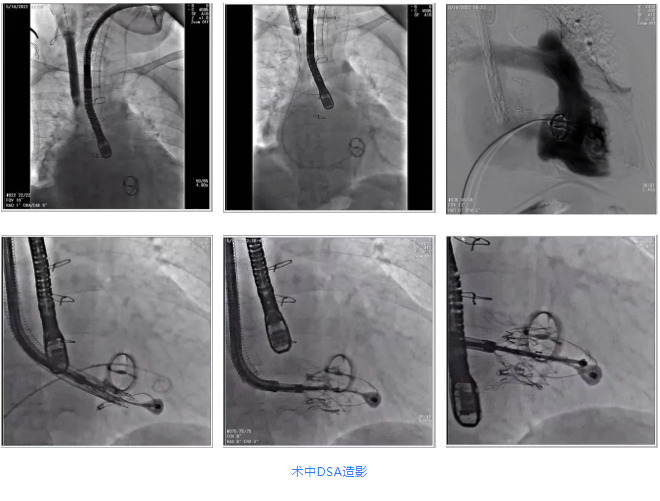

根據(jù)術(shù)前評(píng)估結(jié)果,郭應(yīng)強(qiáng)教授團(tuán)隊(duì)為患者量身定制了手術(shù)策略,決定使用LuX-Valve Plus經(jīng)血管三尖瓣置換系統(tǒng)開(kāi)展手術(shù)治療。手術(shù)在全麻下進(jìn)行,采用經(jīng)右側(cè)頸靜脈入路,在經(jīng)食道超聲和DSA的指引下調(diào)整輸送器角度以達(dá)到正確位置,勾住前瓣后逐步釋放盤(pán)片,盤(pán)片打開(kāi)后順利扎針,最終完成瓣膜植入,輸送器撤出。術(shù)后超聲提示人工三尖瓣同軸性良好,瓣架固定牢靠,無(wú)反流和瓣周漏,術(shù)后三尖瓣平均跨瓣壓差為1 mmHg。